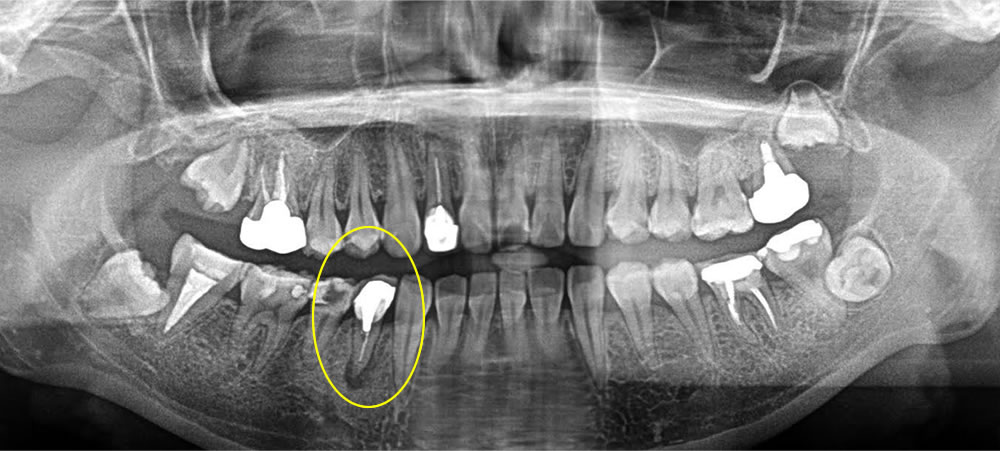

保存不可能な歯を即日インプラントで治療した症例

こちらの患者さまは、右下の歯が痛く、他院にて残す事ができないと診断されたのことでインプラント治療の症例数が多い当院へ来院されました。

まず保存不可能な歯を抜いた後、中に溜まっている肉芽を全て除去し、即日でインプラント埋入を行い、骨の無くなっている所は骨を作る処置を行いました。しっかりと縫合し、歯茎に包帯のような物を付けて終了しました。この包帯は1週間後に除去し、糸は2週間後に取っていきました。